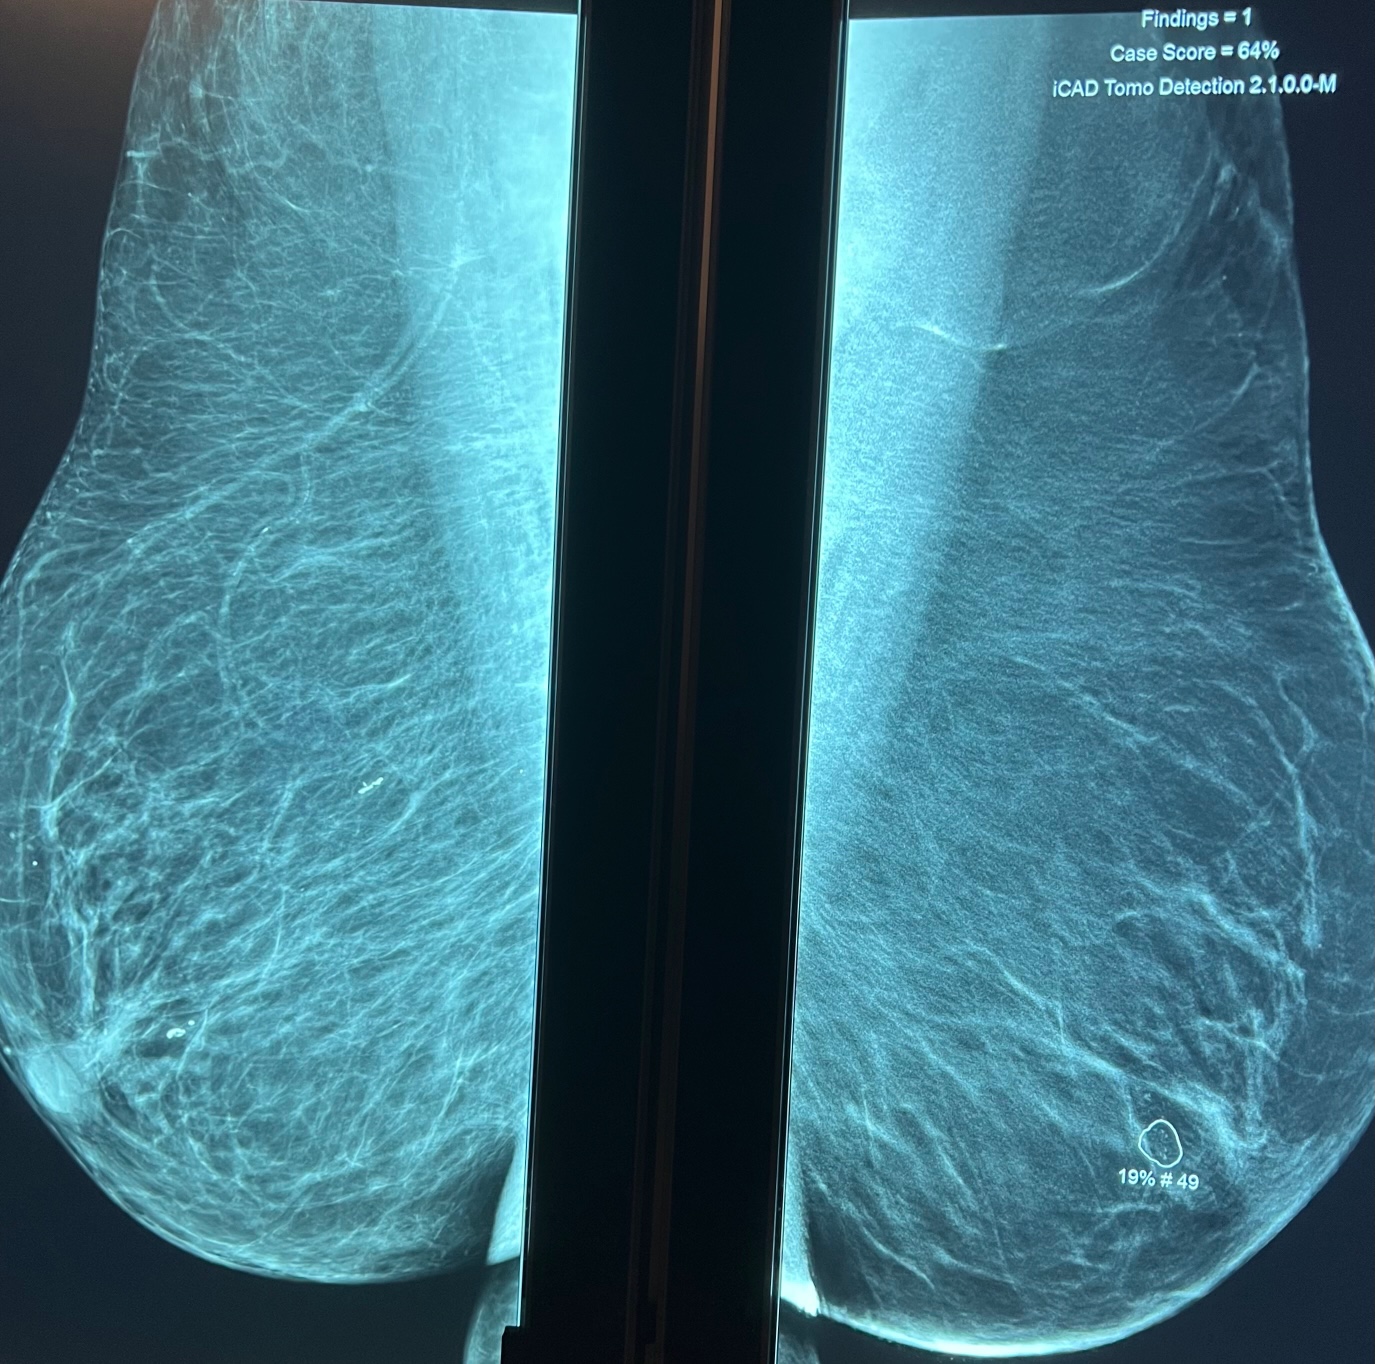

Le radiologue lit votre mammographie et dans un second temps utilise sur le mammographie numérique un CAD (computed aided detection), de dernière génération (ICAD pour imagerie 2D et tomosynthèse 3D) qui va marquer les micro-calcifications (marquées par un carré) et les masses (marquées par un rond) avec la valeur prédictive positve en faveur d'une lésion maligne.

Micro-calcifications (carré) Petite masse, distorsion architecturale (rond)

aleur prédictive de lésion maligne 19%